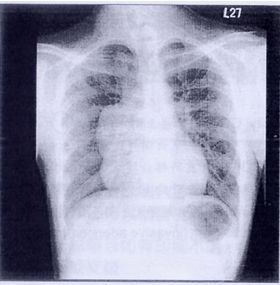

91. 17歲男性因體檢發現有一巨大縱膈腔腫瘤 (如圖),手術切除後診斷為mature teratoma,關於mature teratoma,下列敘述何者正確? (A) 術前之AFP及β-HCG會偏高 (B) 應考慮安排穿刺檢查,確定診斷 (C) 以男性居多 (D) 手術後預後良好